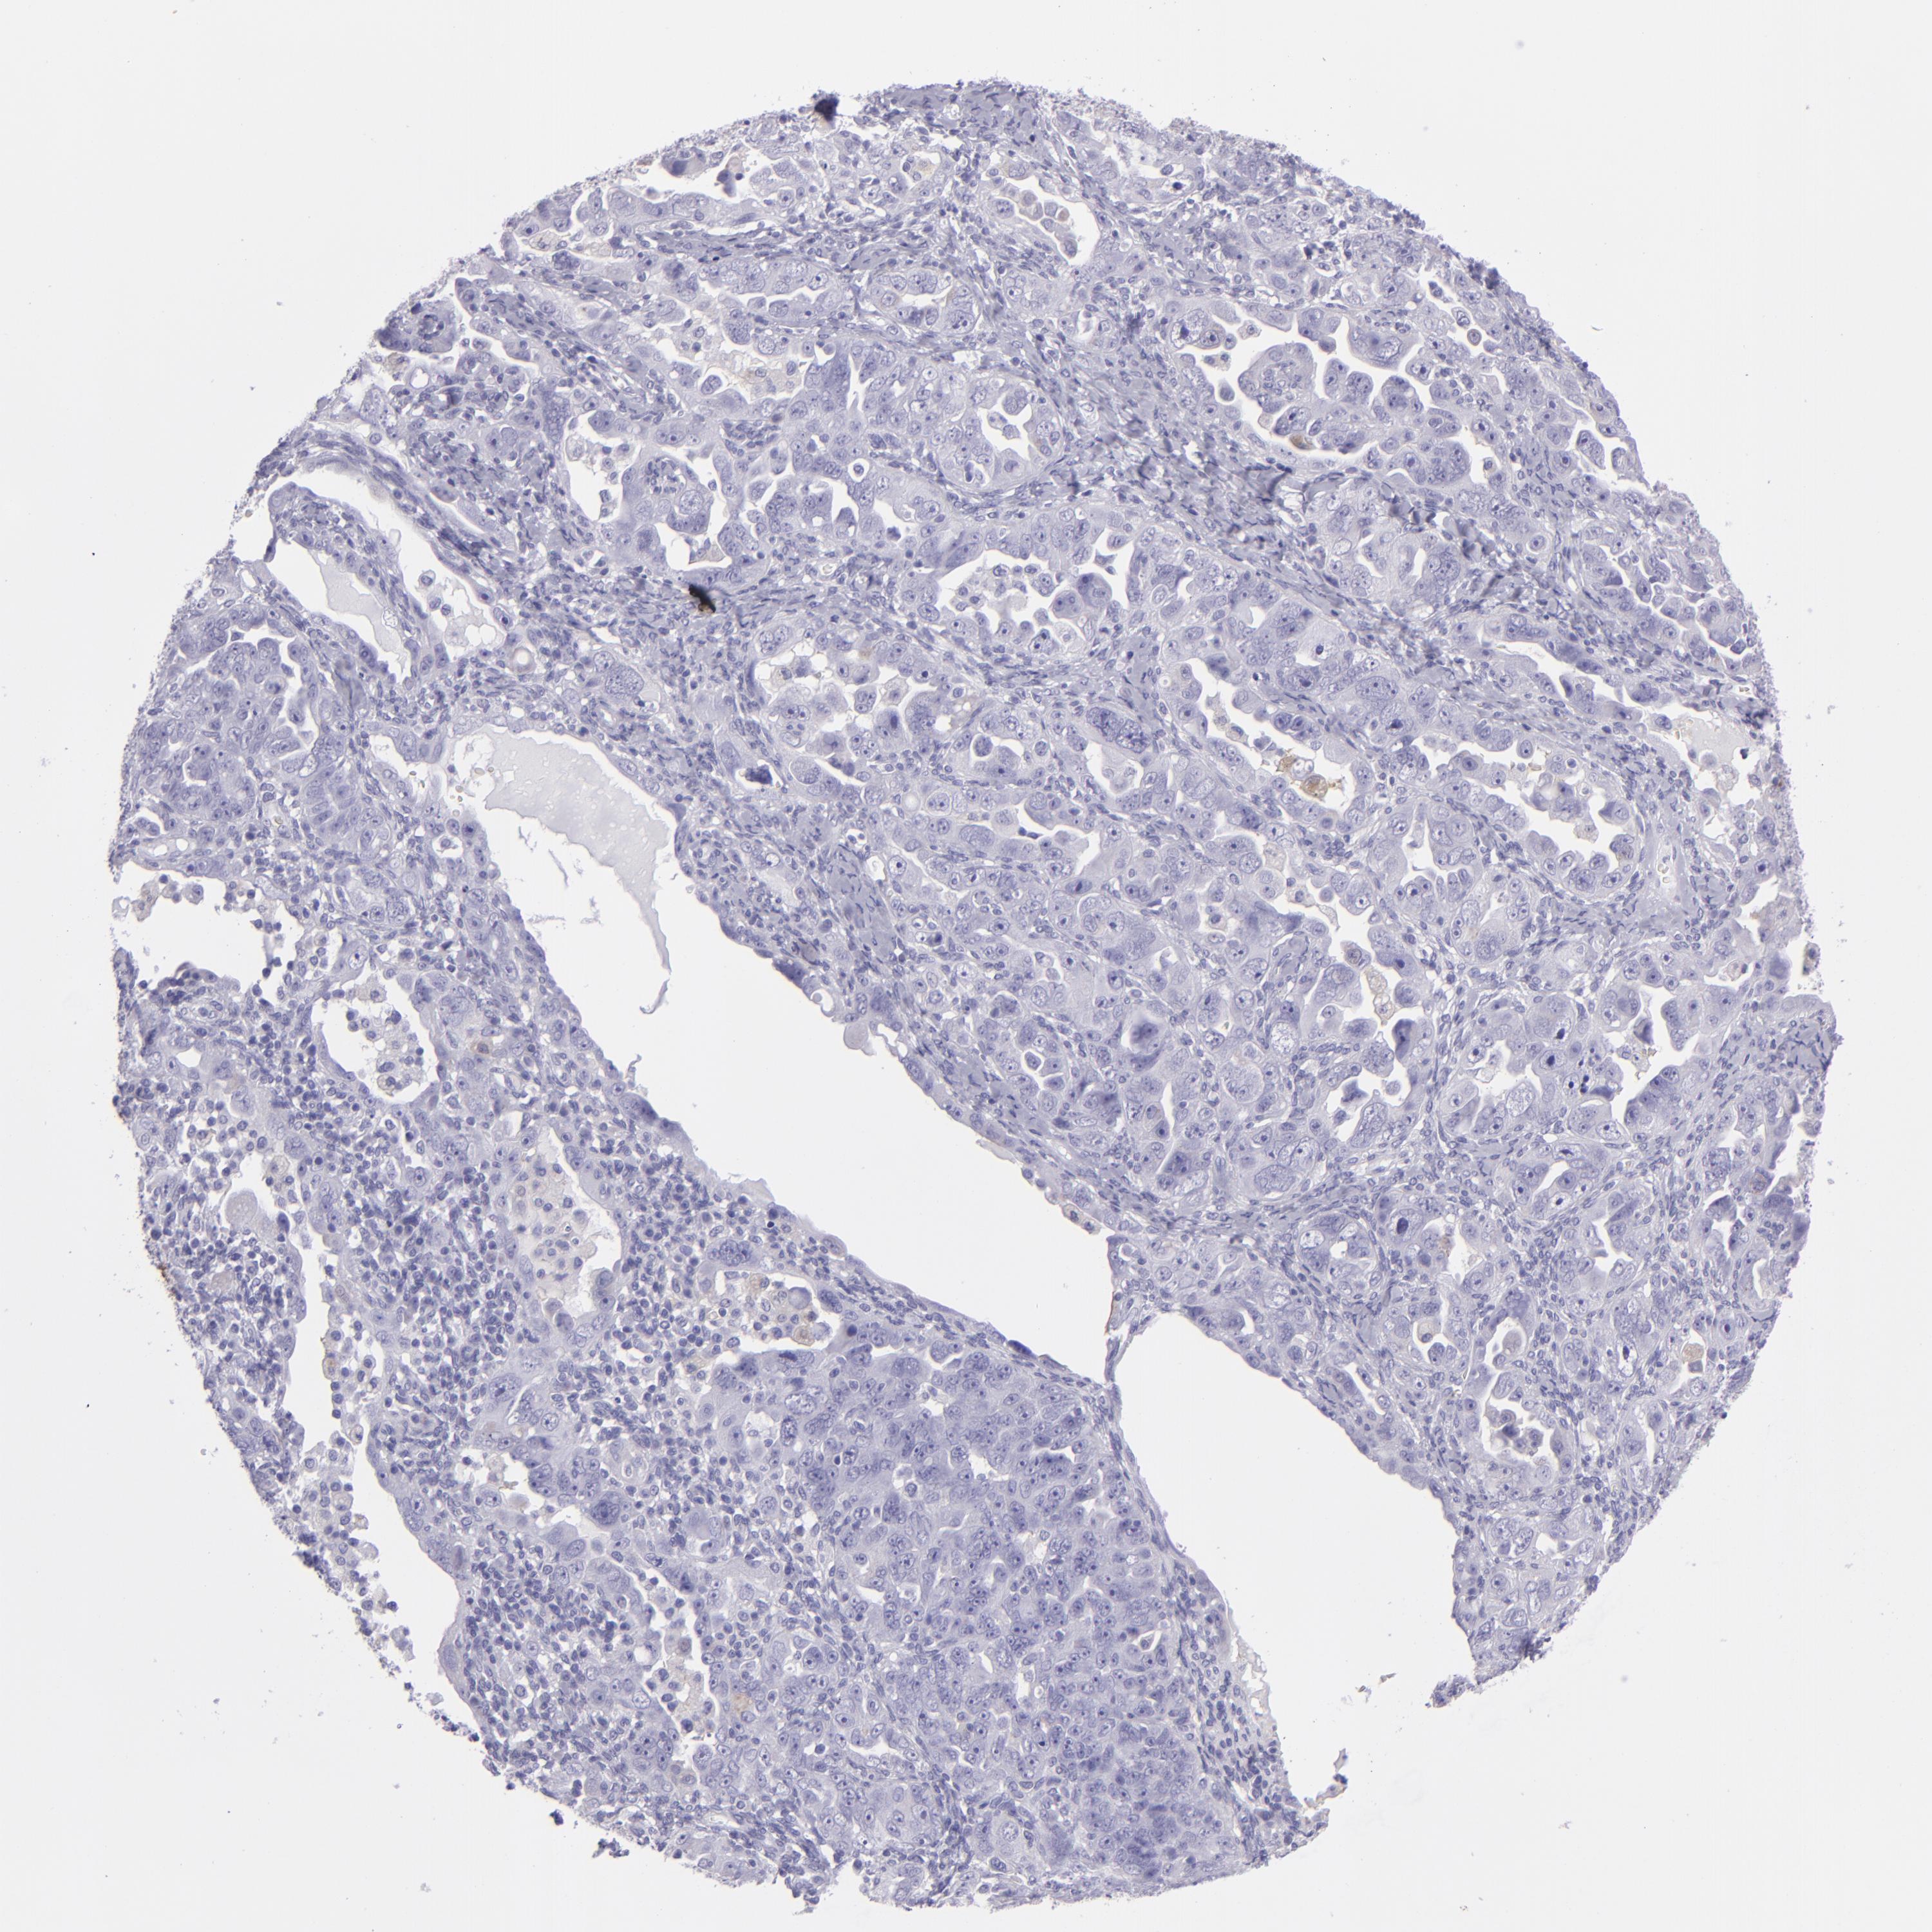

OVARIAN CANCER - Protein expressioni

A mouse-over function shows sample information and annotation data. Click on an image to view it in a full screen mode. Samples can be filtered based on level of antibody staining by selecting one or several of the following categories: high, medium, low and not detected. The assay and annotation is described here.

Note that samples used for immunohistochemistry by the Human Protein Atlas do not correspond to samples in the TCGA dataset.

Antibody stainingi

Antibody staining in the annotated cell types in the current human tissue is reported as not detected, low, medium, or high, based on conventional immunohistochemistry profiling in selected tissues. This score is based on the combination of the staining intensity and fraction of stained cells.

Each image is clickable and will lead to virtual microscopy that enables deeper exploration of all samples and also displays staining intensity scores, fraction scores and subcellular localization as well as patient and tissue information for each sample.

Cystadenocarcinoma, mucinous, NOS

Carcinoma, NOS